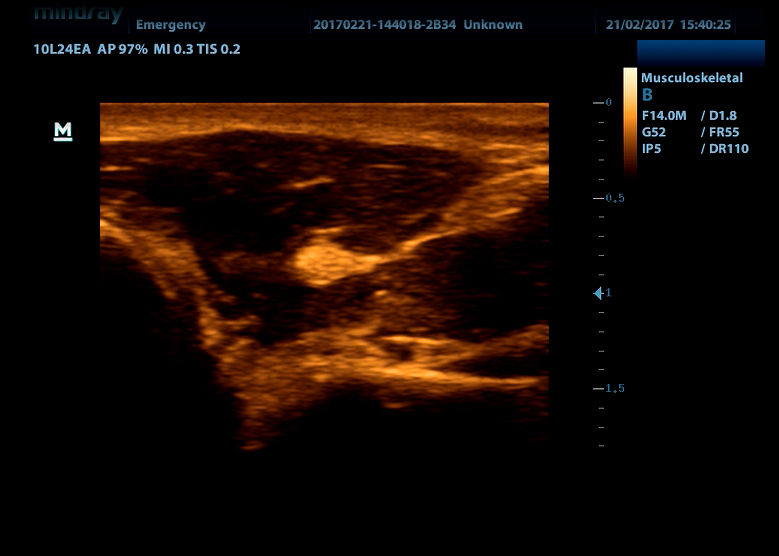

Линейный датчик высокочастотный 10L24EA (8.0/10.0/12.0/14.0/Н10.0/Н12.0 МГц, 24 мм)